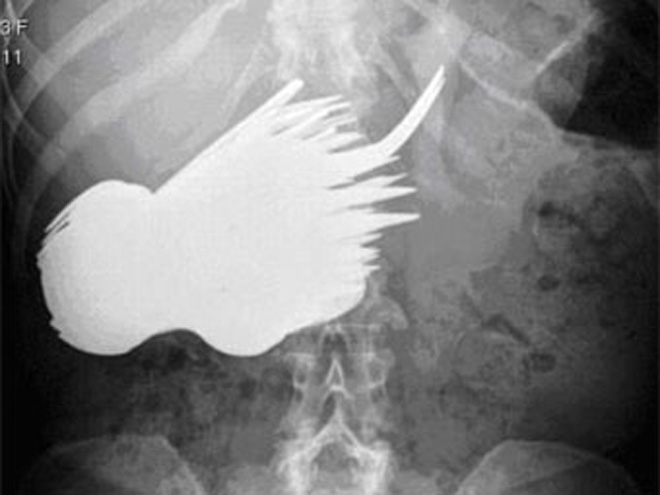

52-летняя Маргарет Даалман, работающая секретарем в одном из роттердамских агентств недвижимости, попала в больницу с жалобами на боли в животе. Рентгеновское обследование показало, что в ее пищеварительном тракте находится множество посторонних предметов.

В ходе экстренной операции из живота Даалман извлекли 78 серебряных ложек и вилок. Позднее она сообщила врачам, что "захотела поесть серебра и не могла удержаться". Выяснилось, что раньше женщина уже была замечена за поеданием столовых приборов, но не в таких больших количествах.